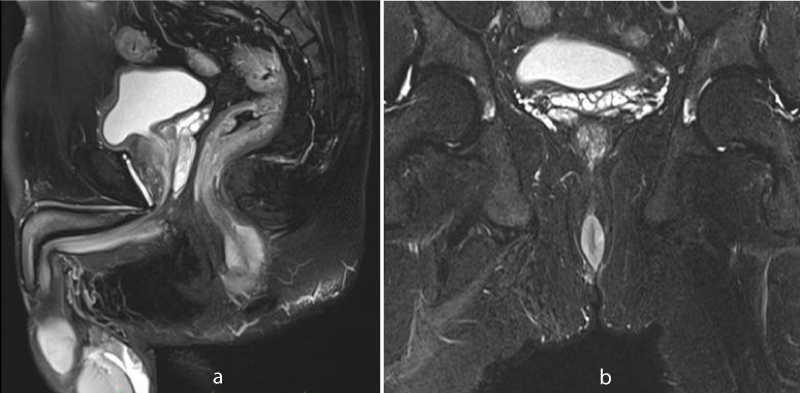

MR imaging revealed short segment circumferential wall thickening of the anal canal with lower margin approximately 1.7cm from anal verge. It was nearly 3 cm in length and 7mm in maximum thickness. The wall thickening showed hyperintense signal in T1-weighted images and T2-weighted images (Figures 1-3). Restricted diffusion with corresponding low signal in ADC map was noted figure 4. Post gadolinium T1-weighted fat saturated images showed hyper enhancement of the wall thickening (Figure 5). The thickening was involving the internal sphincter. No invasion of intersphincteric plane and external sphincter was noted. No extension into perianal fat was noted. Few enlarged heterogenously enhancing lymph nodes were noted in right inguinal region largest 23 x 21 mm in size. The patient underwent wide local excision with right inguinal dissection and adjuvant loco-regional radiotherapy. The histopathological examination showed features suggestive of primary anal malignant melanoma (Figure 6). In routine follow up, the patient showed no features of local recurrence or distant metastasis.

Figure 3: Sagittal (a) and coronal (b) T2-weighted fat saturated MR image shows hyperintense signal of anal canal wall thickening.